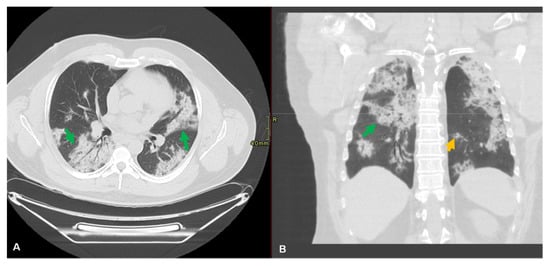

9.5. Radiological Diagnosis